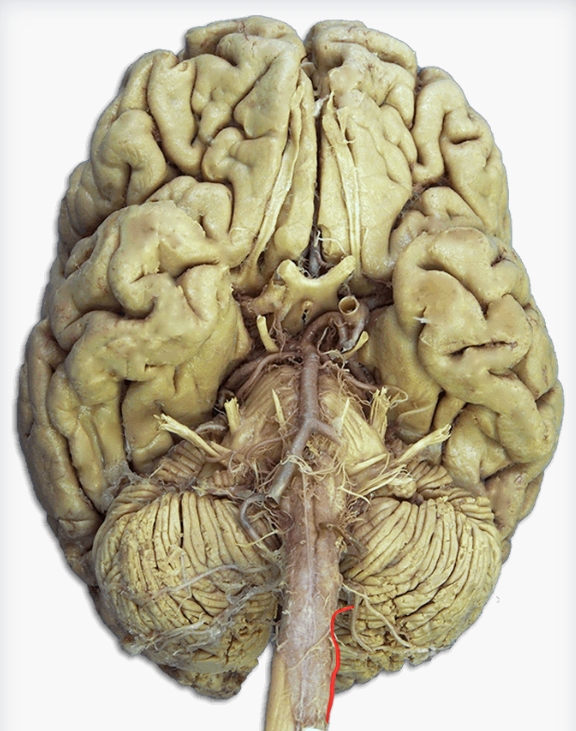

Label this cranial nerve

Olfactory (CN I) nerve

Label this cranial nerve

Optic (CN II) nerve

Label this cranial nerve

Oculomotor (CN III) nerve

Label this cranial nerve

Trochlear (CN IV) nerve

Label this cranial nerve

Trigeminal (CN V) nerve

Label this cranial nerve

Abducens (CN VI) nerve

Label this cranial nerve

Facial (CN VII) nerve

Label this cranial nerve

Vestibulocochlear (VIII) nerve

Label this cranial nerve

Glossopharyngeal (CN IX) nerve

Label this cranial nerve

Vagus (CN X) nerve

Label this cranial nerve

Accessory (CN XI) nerve

Label this cranial nerve

Hypoglossal (CN XII) nerve